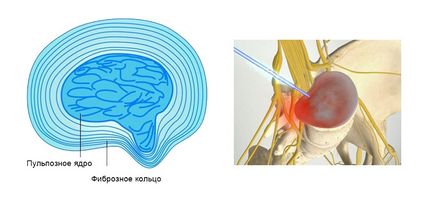

Sérv nyaki gerinc - jelentése razyv külső, rostos ( „ROM shell”), és kilép porckorong belső (a belső lemez tartalma) a gerinccsatorna kompressziós gerincvelői idegek.

Porckorongsérv nyaki gerinc megnyomja gerincvelői idegek okozza keringési zavarok. Véráram hiánya gyulladáshoz vezet az ideg és a fájdalom kialakulásában.